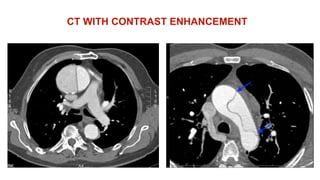

-CT WITH CONTRAST ENHANCEMENT:

- 95% SENSITIVITY

- QUICK

- COMMONLY AVAILABLE

- CAN OBTAIN IMAGES OF PLEURA, NECK, HEAD

VESSELS, PERICARDIUM

- BUT:

- THE PATIENT IS AT RISK OF CONTRAST NEPHROPATHY

CT WITH CONTRAST ENHANCEMENT